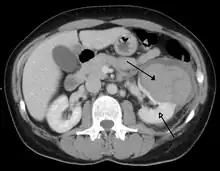

| Abdominal trauma resulting in a right kidney contusion (open arrow) and blood surrounding the kidney (closed arrow) as seen on CT | |

Kidneys

The kidneys may also be injured; they are somewhat but not completely protected by the ribs.[6] Kidney lacerations and contusions may also occur.[13] Kidney injury, a common finding in children with blunt abdominal trauma, may be associated with bloody urine.[13] Kidney lacerations may be associated with urinoma or leakage of urine into the abdomen.[4] A shattered kidney is one with multiple lacerations and an associated fragmentation of the kidney tissue.[4]